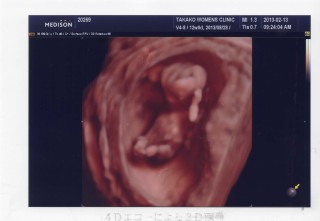

一週間ぶりの検診でした。予定日は2月5日です。 5cmと言われ、体をうねうね動かしてるのがわかりました。 この日は4Dも見せていただき、正座をしながら指をくわえてる姿が見れました。

4Dで撮ってもらいました。

手で顔を隠してる姿かな?

見た瞬間愛しくて感動しました。